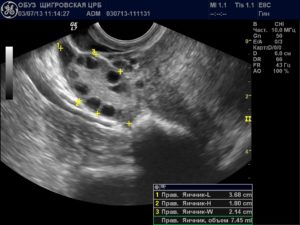

Расшифровкой данных ультразвукового исследования должен заниматься только квалифицированный специалист. На первом УЗИ специалист определяет:

- Наличие каплевидного или округлого гипоэхогенного образования, диаметр которого составляет 0,3-0,5 см. От срока зависит и размер.

- Образование должно быть окружено тонкой оболочкой. Данное образование и есть плодное яйцо.

- Наличие желтого тела.